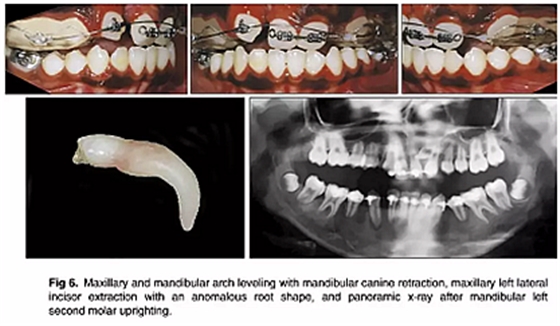

如全景片所示,下頜左側(cè)第二磨牙直立得以實現(xiàn)(圖6)。1年后,去除上頜擴(kuò)弓器,上下牙弓完全吻合。在上下牙弓中,用0.017×0.025英寸的鎳鈦弓絲進(jìn)行整平。上頜左側(cè)尖牙被移至側(cè)切牙位置; 下頜第一前磨牙被拔除,尖牙開始縮回。

隨后,由口腔頜面外科醫(yī)生(圖6 ; 圖7)拔除左右側(cè)側(cè)切牙,并使用直角弓來旋轉(zhuǎn)上頜磨牙并改善牙弓形態(tài); 在下頜弓中,尖牙的牽引繼續(xù)(圖7)。